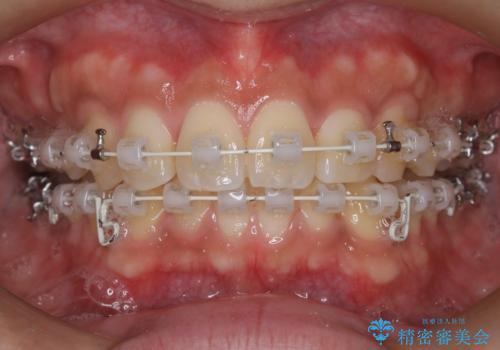

- 矯正装置

- 審美装置

最初はインビザラインを治療していた経緯がありますが、使用時間が確保できずワイヤー矯正へ移行しております。